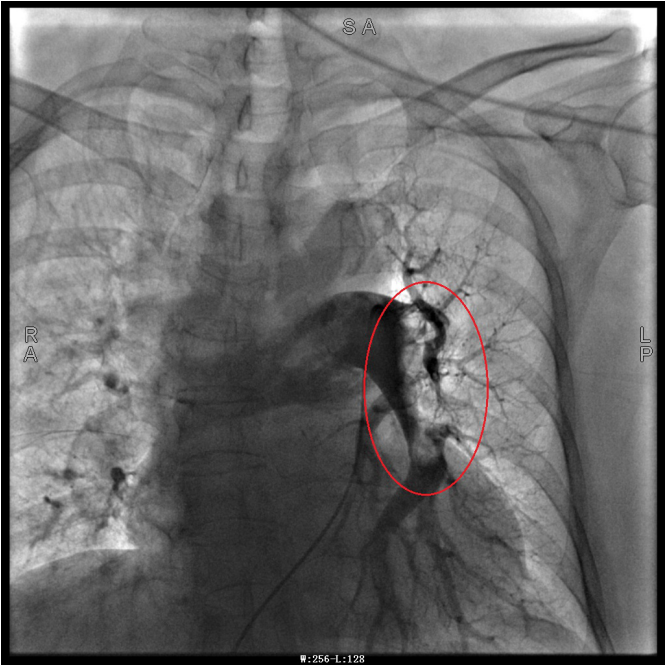

譚婆婆今年已經(jīng)72歲了,因“突發(fā)意識障礙2次”到璧山區(qū)人民醫(yī)院神經(jīng)內科治療。譚婆婆沒有基礎心臟病病史,但近段時間活動耐量明顯下降,稍做活動就出現(xiàn)呼吸困難。入院后查BNP及心臟彩超均未提示明顯異常,查D二聚體明顯升高,經(jīng)心血管內科周波醫(yī)師會診后轉入科室繼續(xù)治療。在心血管內科主任、內科學(心血管病)博士于長青的指導下,周波醫(yī)師成功完成醫(yī)院首例“一站式”微創(chuàng)介入手術。在影像中,可以清晰地看到堵塞的血管經(jīng)溶栓治療后,重新暢通無阻,流動起支撐生命的血液。

肺動脈造影技術是目前診斷肺動脈栓塞的“金標準”,在全程心電監(jiān)護下,通過股靜脈或者頸內靜脈置入鞘管后,利用導絲引導,將造影導管送入肺動脈;可在左/右肺動脈主干及其左右分支內,分別進行肺動脈造影或選擇性肺動脈造影,存在栓塞的肺動脈血管在造影劑注入后即會顯示出充盈缺損、充盈緩慢、或者血管顯影模糊,嚴重栓塞的肺動脈血管甚至會出現(xiàn)血流截斷征象。

注明:第一張、第二張為術前圖像